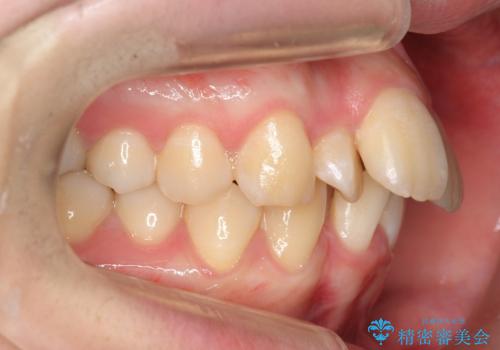

20代女性 前から5番目の歯を抜歯

- 前歯のがたつき、前突を主訴に来院。

治療は長くかかりましたが、正常な形の歯をのこすことができました。